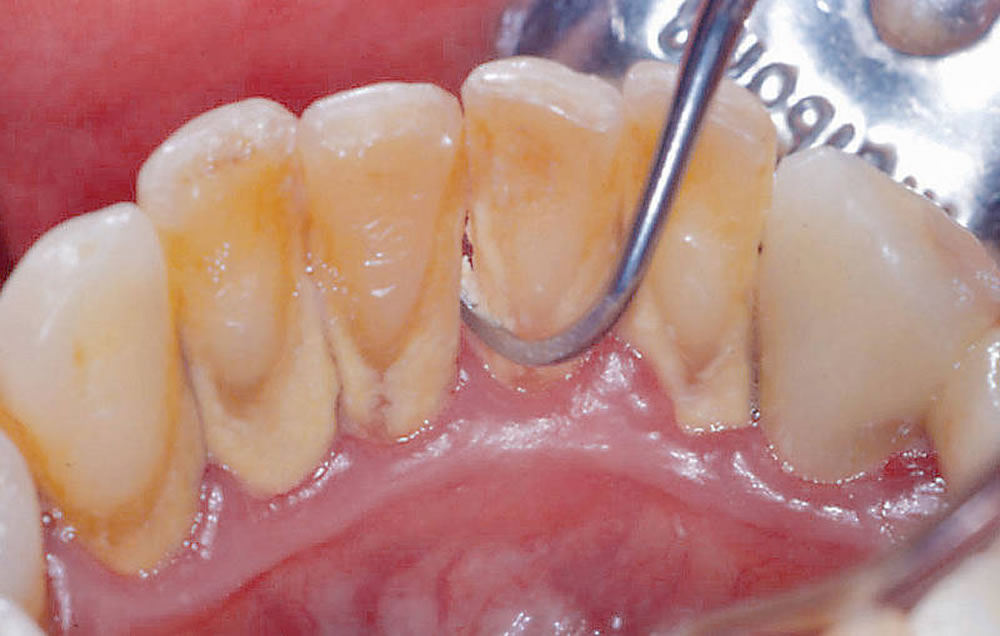

歯科検診・クリーニング

お口の状態を把握するため、歯科検診を行います。虫歯や歯周病を予防するため、歯石の除去・歯面のクリーニングを実施いたします。

また、セルフケアの質の向上のため、必要に応じて歯磨き指導なども行います。